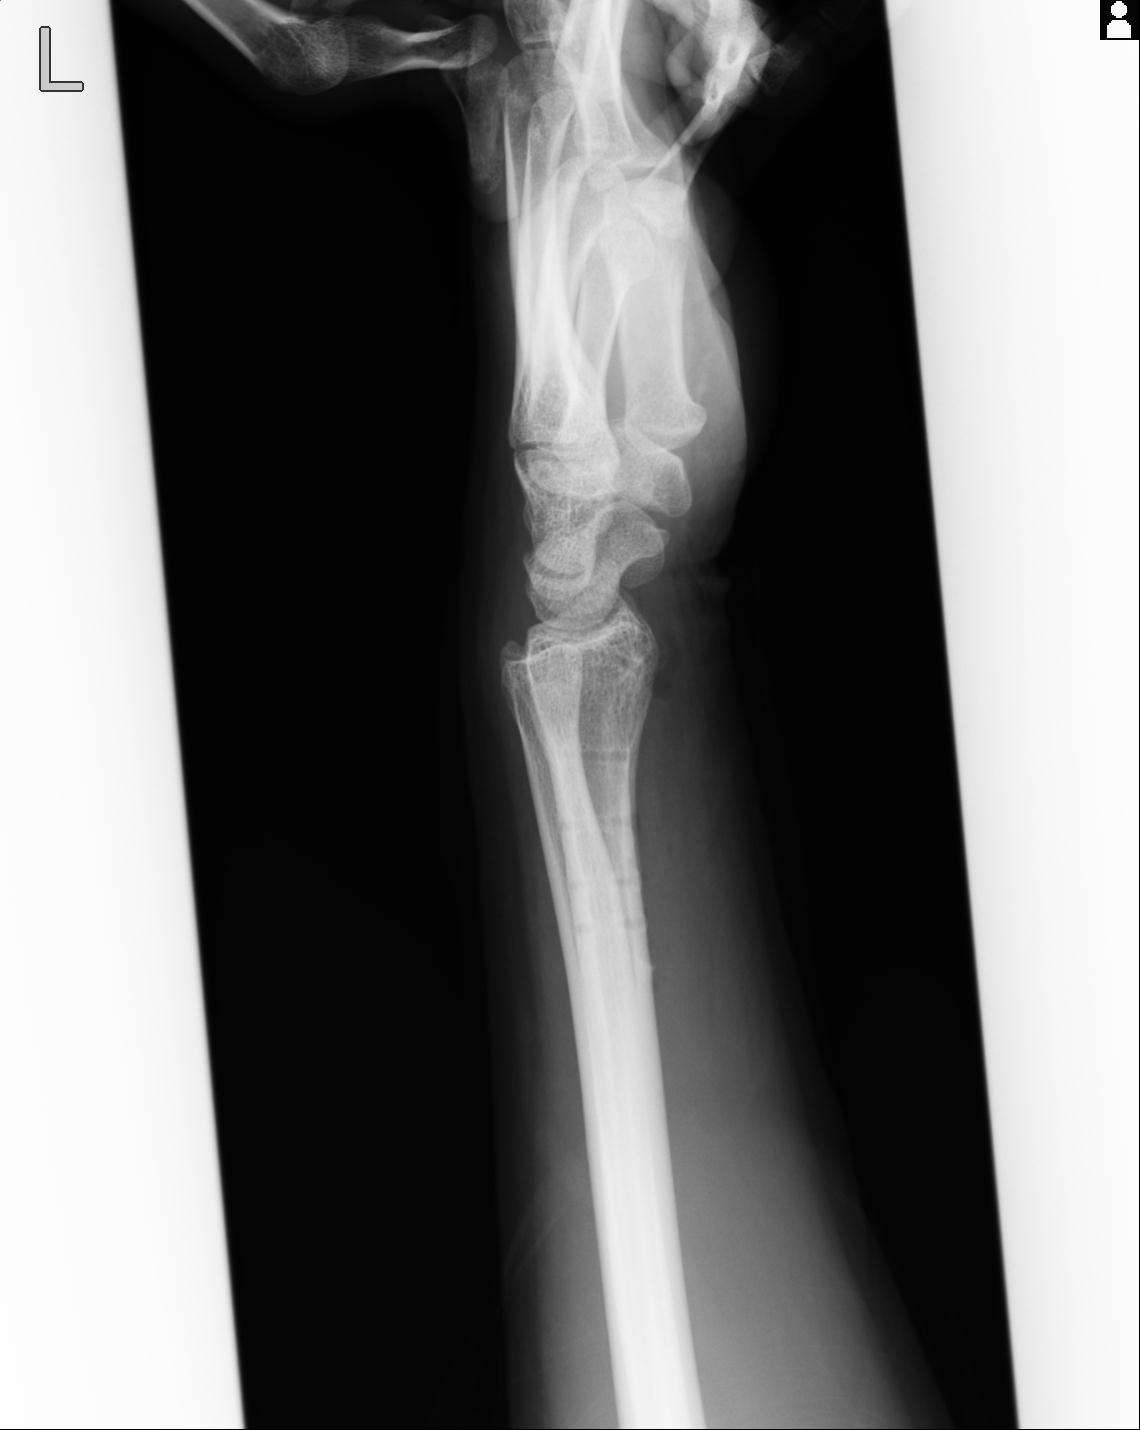

110214 12/20 肩 2R 12/21 肩 4R 72歳女性 左上腕外科頚プレート